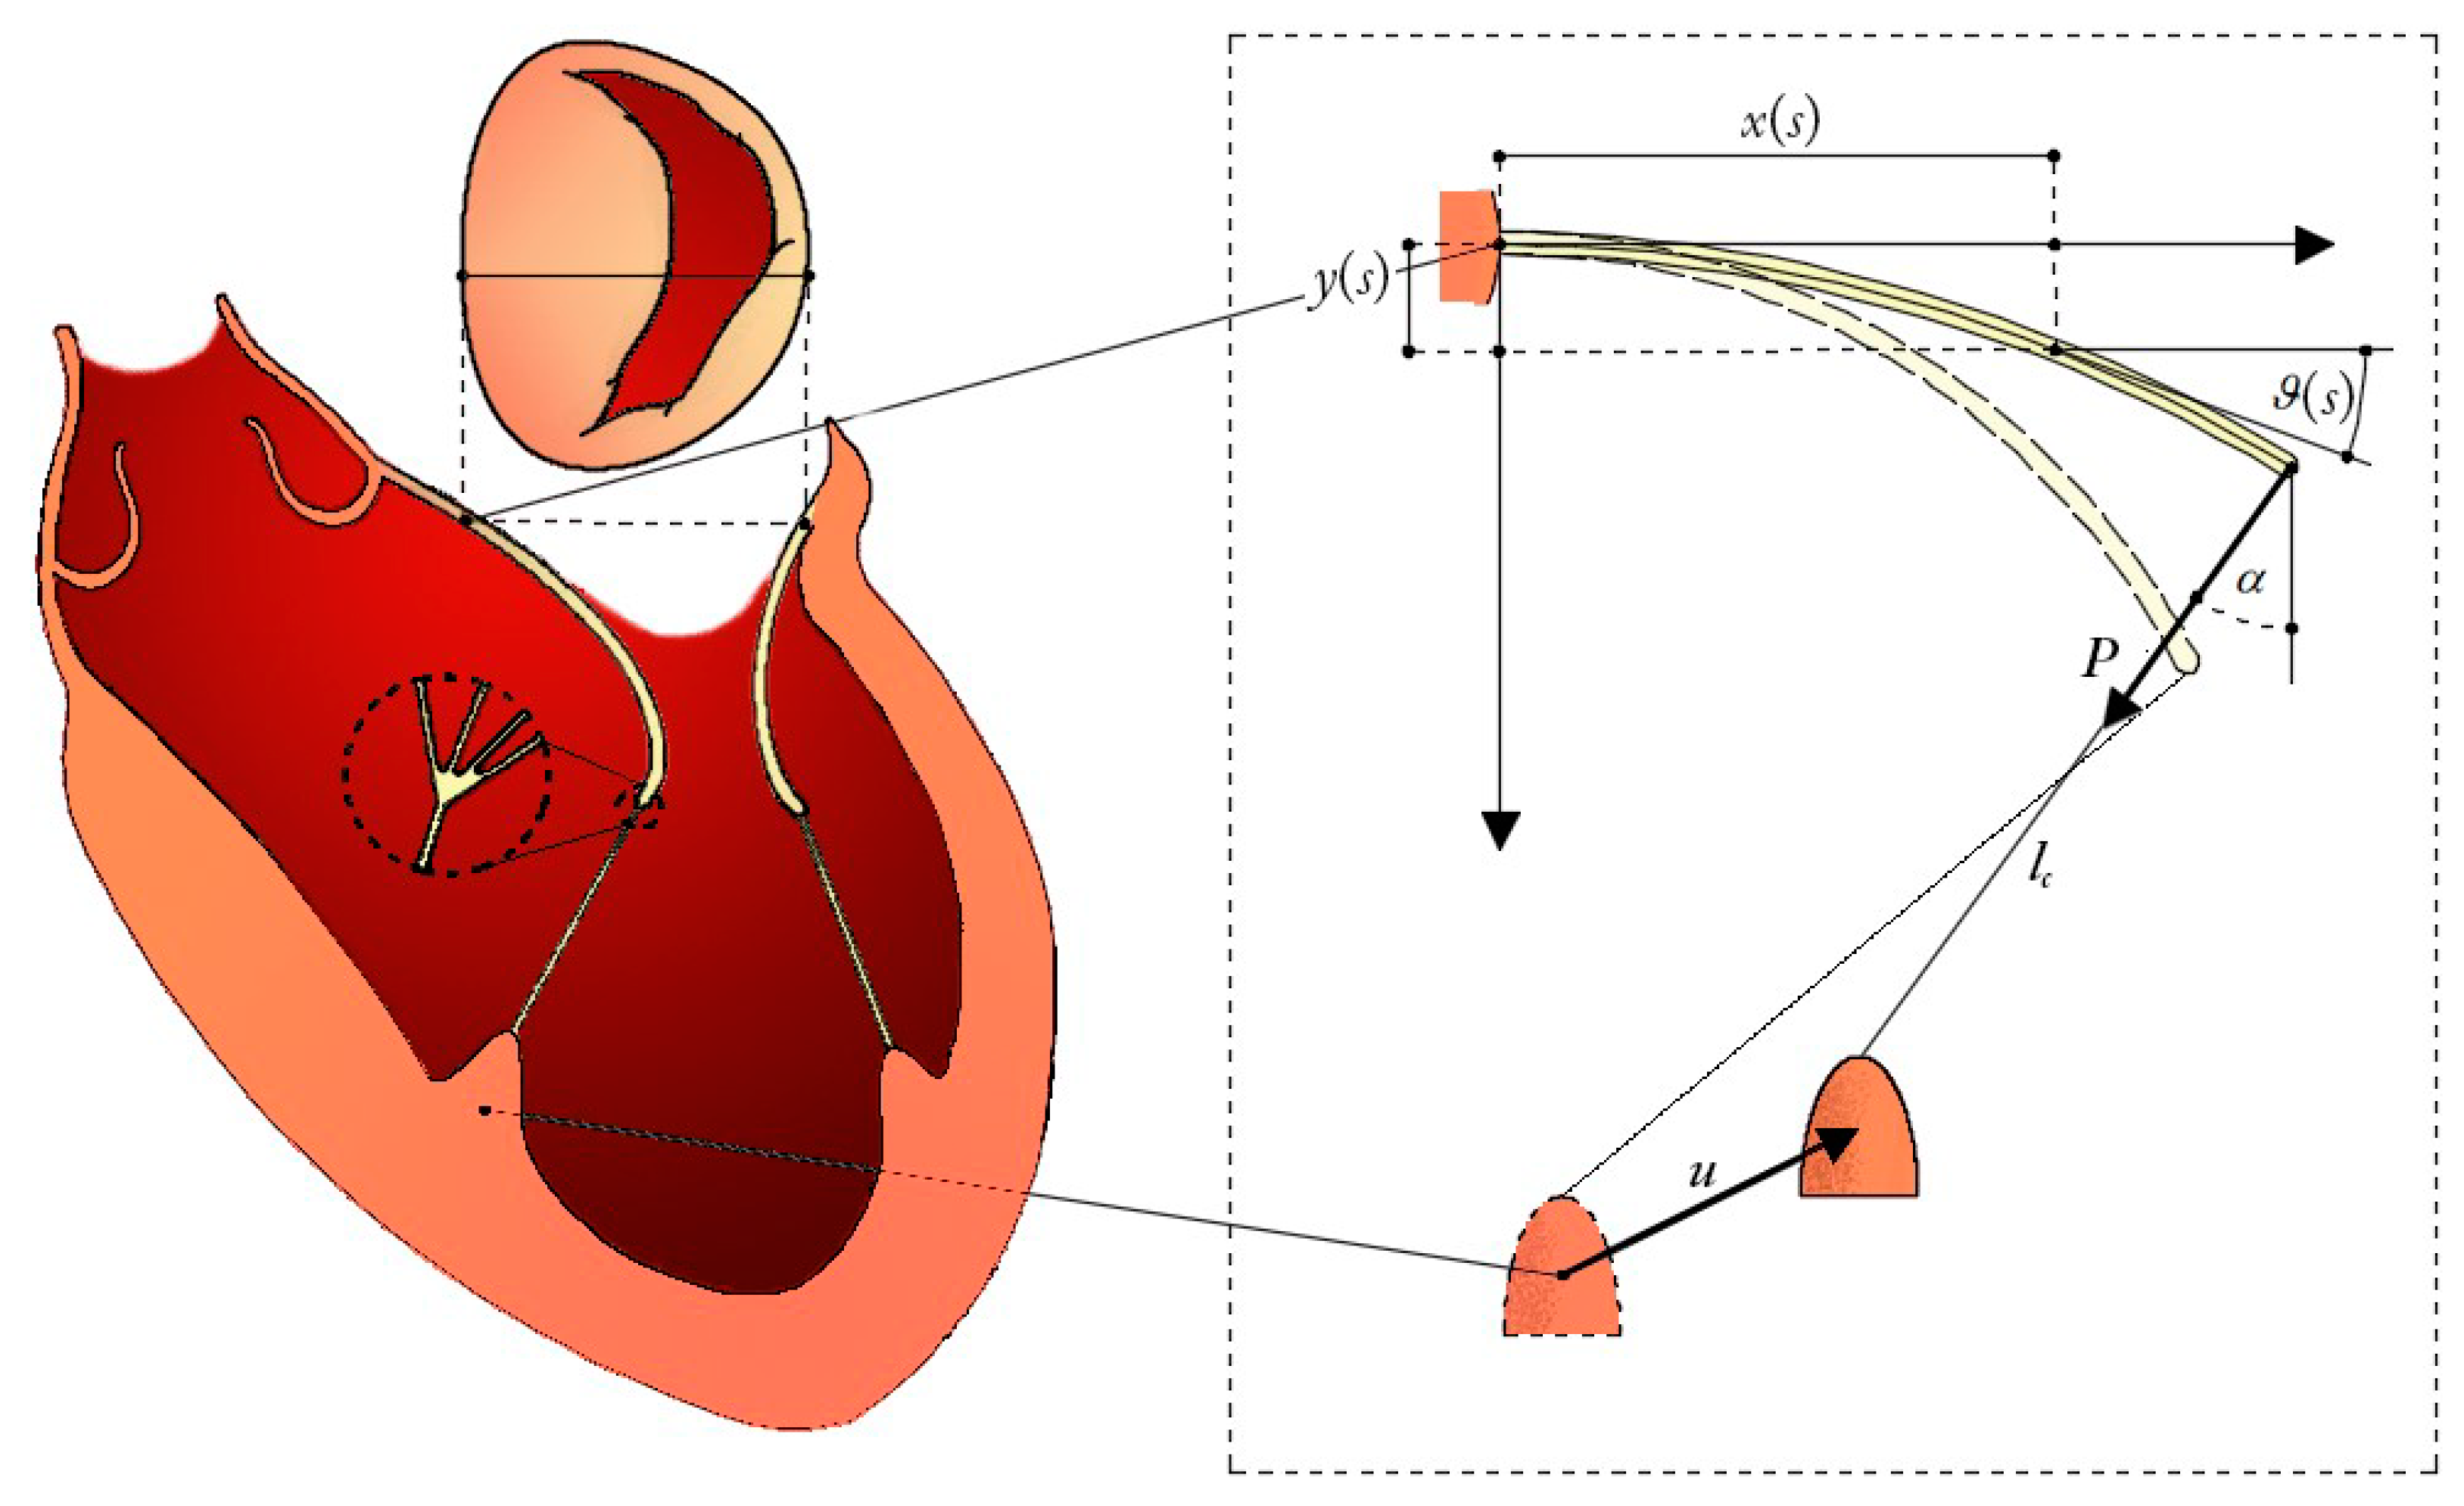

2.1. Mitral Leaflets Modelled as Euler’s Elastica

2.2. Hyperelasticity of the Chordae Tendinee

2.3. Chorda-Leaflet Coupling and Overall System Interaction